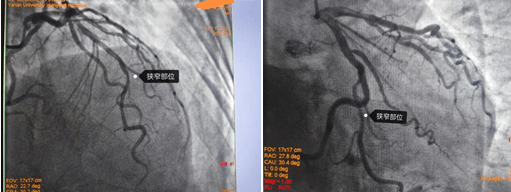

造影结果右冠多处狭窄约70-90%,左冠也是多处70-80%狭窄;对于这样一个结果,是这些狭窄造成的胸闷、心悸吗?这些病变需不需要都给予介入处理呢?一根血管植入支架还是三根血管都需要植入支架?心内九科崔旭辉主任带领介入医生团队讨论后,决定进行RFR检查给出一个明确的答案。所以经过与患者及其家属沟通后选择进行RFR检测,结果如下图:

RFR静息全周期比值,是最新的评价冠状动脉的功能学指标。相比传统的FFR检查,RFR检查无需使用最大充血药物,避免了患者不适,更简单、安全,而且手术时间更短,效率更高。通过RFR指导冠状动脉介入治疗,可以改善患者预后,节约医疗费用。崔旭辉介入团队在心导管室技师的协助下,半小时内完成左右冠脉内RFR检查,结果分别是:0.92,0.97,0.96;根据客观的检查结果,患者三支血管都不需要植入支架,马先生一家高兴地放下了思想包袱,开心回到病房,继续药物治疗。